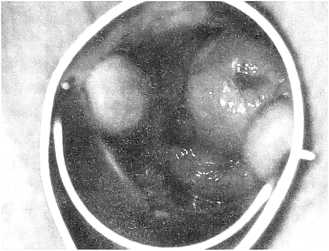

При осмотре с помощью кольпоскопа слизистой влагалища на боковых стенках могут выявляться папиллообразные разрастания от единичных до множественных в виде шиповидных выпячиваний (рис. 6, 7) или «сочных» образований слизистой (рис. 8) и экзофитных кондилом (рис. 9).

Рис. 8. Единичная папиллома слизистой влагалища

Рис. 9. Множественные кондиломы слизистой влагалища